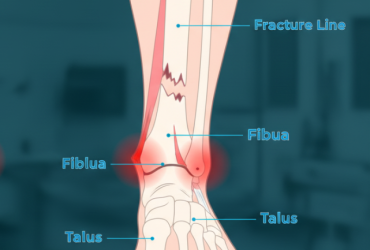

Ankle Fractures – breaks in one or more ankle bones, usually due to trauma or falls.

Ankle Fractures

An ankle fracture is a break in one or more bones of the ankle joint, often caused by twisting injuries...